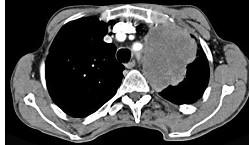

问题 56岁,男,意识错乱情绪不稳定一周,请结合胸片和CT,选出最可能的诊断 ( )

选项 A、韦格肉芽肿 B、胸腺瘤 C、错构瘤 D、胸内甲状腺肿 E、肺癌

答案 E